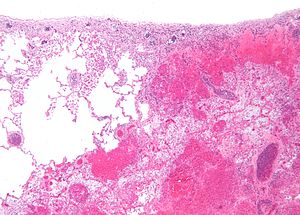

Pulmonary infarct. H&E stain. | |

| LM | necrosis of alveolar walls - loss of nuclei, alveolar hemorrhage, +/-evidence of underlying cause |

Microscopic

Features:

- Necrosis of alveolar walls - loss of nuclei.

- Alveolar hemorrhage.